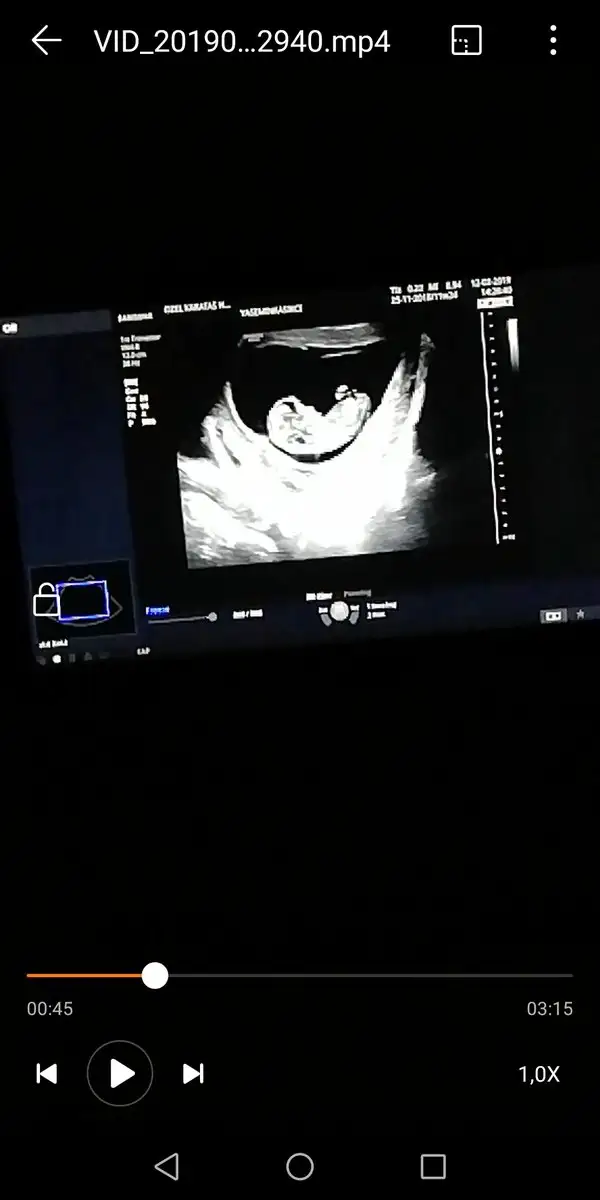

Bak aynı doktor aynı makine bu da kızım 7+2 :) demek istediğim bu

Gözün aydın :) kese konumuna göre sağ da mıydı solda mı ? Benim kızım sağdaydı. Bu gebelikte solda. Kızlar Buda kız dedi ama ben erkek hissediyorum :deli: